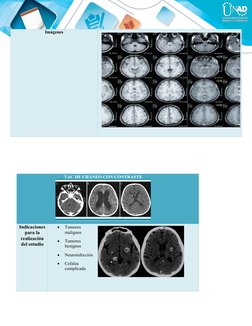

TAC DE CRÁNEO CON CONTRASTE

Indicaciones  Tumores

para la malignos

realización  Tumores

del estudio benignos

 Neuroinfección

 Cefalea

complicada

Preparación  Ayunas

del paciente  Estar hidratado

 Canalizar al paciente en el pliegue del brazo (utilizar yelco No 18 o 20)

 Tasa de filtración glomerular.

 Examen de BUN y Creatinina.

Imágenes